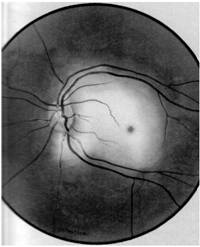

- Edemul retinian poate fi asociat cu hemoragii retiniene; daca este izolat retina are un aspect alb laptos (Fig. 20.1). Poate fi localizat:

fie in periferie, cand este asimptomatic;

fie in zona centrala, realizand edemul traumatic Berlin, care determina o importanta scadere a acuitatii vizuale, uneori ireversibila. Aspectul fundului de ochi este comparabil cu cel din ocluzia de artera centrala a retinei, toata zona polului posterior fiind ocupata de edem alb

Fig. 20.1 Edem traumatic Berlin

ischemic,

macula contrastand prin culoarea rosie ciresie. Arterele si

venele sunt foarte ingustate. Afectiunea apare dupa o lovitura

directa a globului ocular (minge de tenis, bulgare de

zapada).

Din punct de vedere fiziopatologic, modificarile apar datorita unor tulburari exsudative

determinate de compresiunea arterelor ciliare in traiectul lor scleral. Prezenta edemului retinian impune in functie de severitatea acestuia, un tratament vasodilatator si angioprotector, uneori corticoterapie pe cale generala.